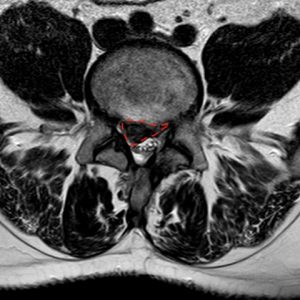

La hernia discal lumbar es una lesión del disco con salida de material al canal, foramen o margen lateral discal (extraforaminal). Se trata, por lo tanto, de un diagnóstico radiológico. En función de la cantidad de disco migrada al canal se denomina (apreciación un tanto subjetiva) protrusión (poca) o hernia (mucha). En función de si está contenida por el ligamento o no se llama subligamentosa o extruída, respectivamente. Se habla de hernia migrada cuando el material discal se desplaza en sentido craneal o caudal a través del eje.